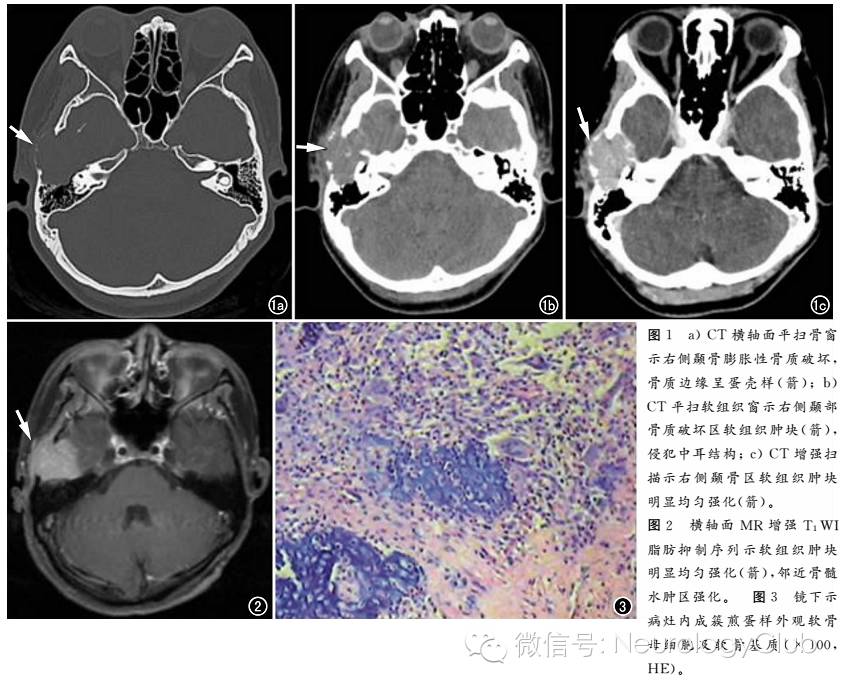

CT表现:右侧颞骨、蝶骨大翼、乳突前部见不规则膨胀性骨质破坏,骨质破坏区不规则软组织肿块影,最大横截面积约32mm×32mm,增强后软组织肿块内明显强化(图1)。右侧听小骨局部受压内移。增强MRI表现:右侧颞骨、乳突前部及右侧颞下颌关节周围示不规则形异常强化信号影,大小约29mm×28mm×28mm。右侧颞叶底部受压变形,病灶部分侵入外耳道及乳突内(图2)。相邻颞骨、乳突前部及外耳道骨壁骨质破坏。CT引导下穿刺活检病理诊断为右侧外耳道、颞骨软骨母细胞瘤,呈侵袭性生长(图3)。

本例发生于42岁女性右侧颞骨区,发病年龄及部位均不典型。对于非典型部位的软骨母细胞瘤由于发生骨较小,骨皮质较薄,因此肿瘤在X线及CT上大部分呈膨胀性、溶骨性骨质破坏,可伴软组织浸润,表现出侵袭性生长的特征。在MRI T1WI上呈低信号,T2WI上呈高信号,与一般骨肿瘤难以区别,而Gd-DTPA增强病灶内无坏死囊变区,可呈明显强化,这与病理上该肿瘤以富于血管的疏松结缔组织内含有大量成骨细胞、骨样组织和成骨组织为特征有关。 颞骨区软骨母细胞瘤临床常见症状有听力减退、耳闷、耳鸣、颞区触及活动较差的质硬肿块等。

软骨母细胞瘤好发于青少年长骨骨骺,表现为局部骨质破坏,周围伴有明显骨髓和软组织水肿。如果发生于上述典型部位,并出现骨质吸收并周围水肿,则诊断容易。但软骨母细胞瘤不仅限于上述典型部位。如本例出现于右侧颞骨,诊断相对困难。但仍然可发现一些有意义的征象。如病变区域骨质膨胀,是病变生长缓慢的征象,从而提示良性病变。颅骨内外板的骨质不连续,提示病变的侵袭性。病变位于颞骨区域的骨质破坏伴周围的水肿,提示可能为相对常见于此部位的三种病变,即骨母细胞瘤、软骨母细胞瘤、Langerhans细胞组织细胞增生症。后者常见于儿童,骨质破坏或吸收边界锐利,似局部的单纯骨质缺损,很少出现骨质膨胀,软组织改变较轻。前两者有时区分较为困难,但骨母细胞瘤病变中心区域常见明显钙化或骨化。由于此例病变中心只有轻微的点状钙化或骨化样高密度影(也可能为破坏残留的骨质),不像骨母细胞瘤中心常见的明显钙化,由此推测,更可能为软骨母细胞瘤。当然,最终需病理学的检查并与影像学结合,得出更准确的诊断。病理诊断为颞骨软骨母细胞瘤累及外耳道,呈侵袭性生长。与影像诊断是符合的。